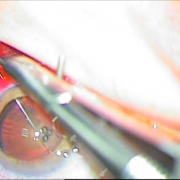

Διαθέτουμε την εμπειρία για χρήση ειδικών τύπων ενδοφακών, όπως είναι οι αστιγματικοί οι πολυεστιακοί, οι ιριδικής στήριξης και πολλών άλλων. Όλα αυτά συμβάλλουν στην αντιμετώπιση του καταρράκτη με ποιοτικό και εξατομικευμένο τρόπο.

ιριδικής στήριξης